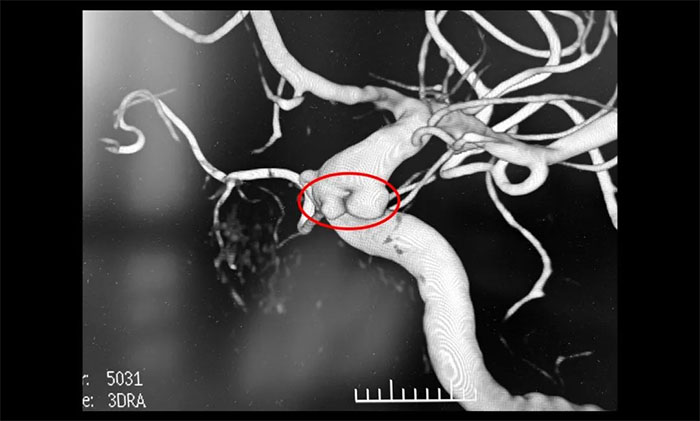

患者为59岁女性。因近期出现头晕、头痛伴视物模糊入院就诊,行磁共振检查发现右侧颈内动脉C6段可疑小突起,考虑脑动脉瘤。行脑血管造影提示,右颈内动脉眼动脉段多发动脉瘤。

▲ DSA提示,右颈内动脉眼动脉段多发动脉瘤

席刚明教授分析认为,该动脉瘤不规则,破裂风险大,建议积极治疗。但该动脉瘤位置不适合显微手术夹闭治疗,而常规支架辅助栓塞难以实现眼动脉起始部动脉瘤栓塞,后期动脉瘤进展及复发风险高,较好的治疗方式为血流导向装置置入。大家一致同意治疗方案,与家属详细解释沟通后,同意进行血流导向装置置入治疗。